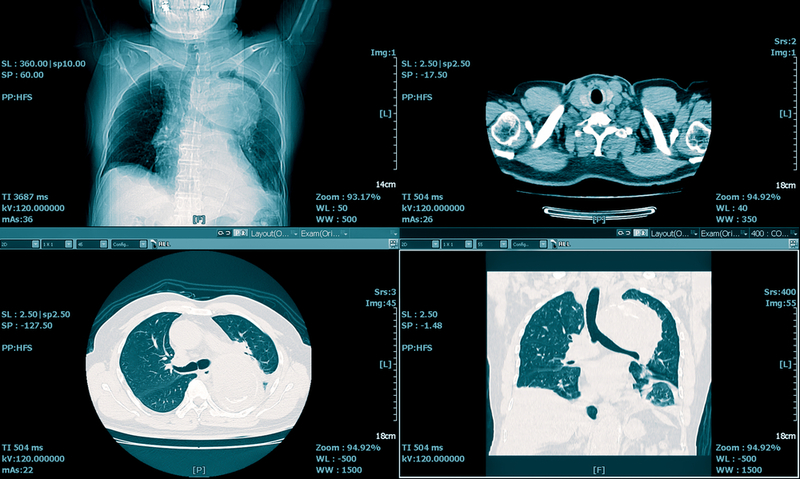

Findings of more extensive GGO than consolidation on chest CT scans obtained during the first week of illness were considered findings highly suspicious of COVID-19, at the point during the COVID-19 outbreak when this study was performed.

Cheng Z, Lu Y, Cao Q, et al. - Researchers examined the clinical features and CT manifestations of coronavirus disease 2019 (COVID-19) by comparing patients with COVID-19 pneumonia with patients with non–COVID-19 pneumonia who presented at a fever observation department in Shanghai, China. Between January 19 and February 6, 2020, individuals were retrospectively included in the study who underwent real-time reverse transcription–polymerase chain reaction (RT-PCR) testing. It was demonstrated that imaging patterns of multifocal, peripheral, pure ground-glass opacities (GGO), mixed GGO, or consolidation with slight predominance in the lower lung and findings of more extensive GGO than consolidation on chest CT scans obtained during the first week of illness were considered findings highly suspicious of COVID-19, at the point during the COVID-19 outbreak when this study was performed.